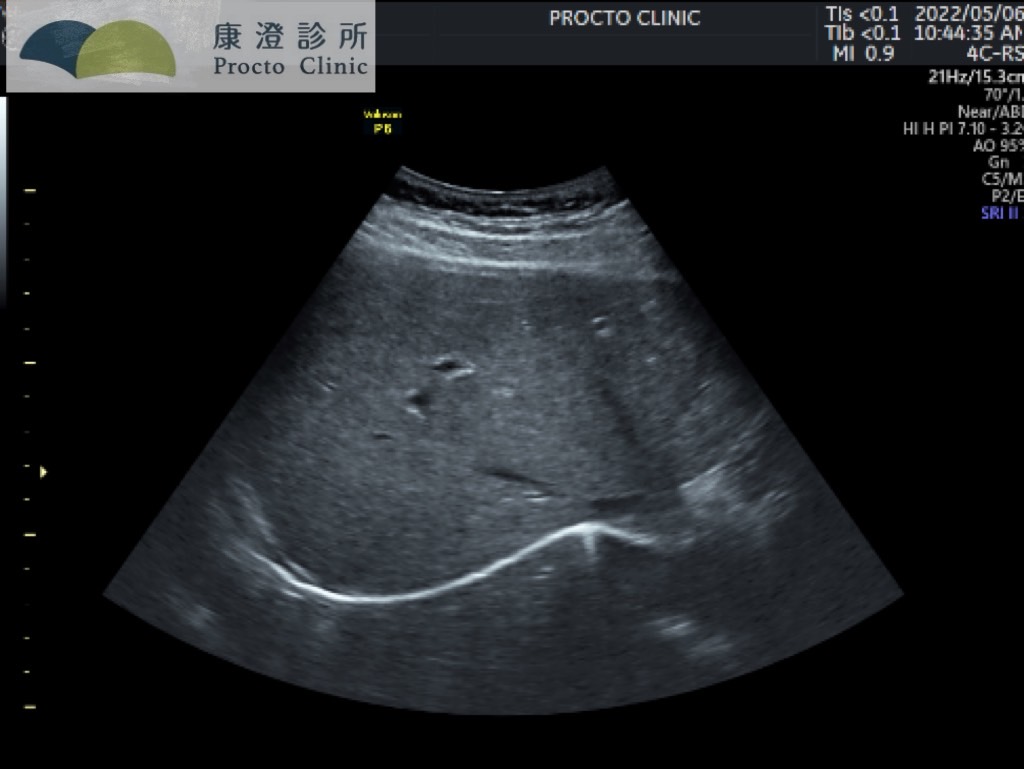

▲諮詢當天剛好有空,順便讓醫師幫小彤掃一下超音波。